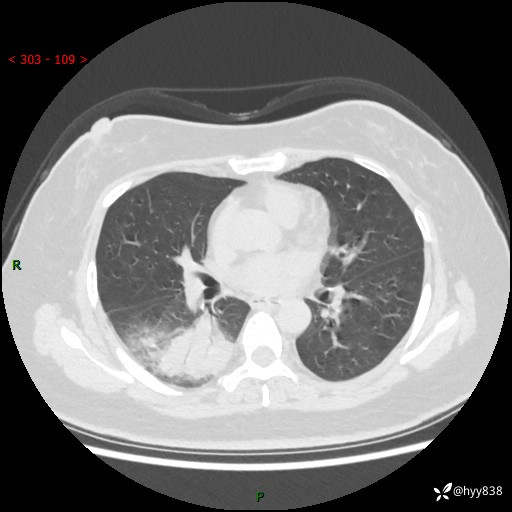

大叶性肺炎的表现形式,晒晒鉴别诊断吧…结果公布~

简要病史:患者8天前无明显诱因出现咳嗽、咳痰,为绿色脓痰,无明显加重与缓解因素,无高热、寒战,无呼吸困难,无大量脓痰,无哮鸣音,于当地医院行胸片示右下肺团块影,性质待定,予口服药物治疗症状未见明显改善,具体药名不详,为求进一步诊治来我院就诊,门诊以“肺占位性病变”收入我科进一步诊治。 患者自发病以来,精神、饮食尚可,睡眠欠佳,大小便正常,体力、体重未见明显异常。

辅助检查:CT

临床诊断:肺占位

胸部CT平扫

增强动脉期+静脉期